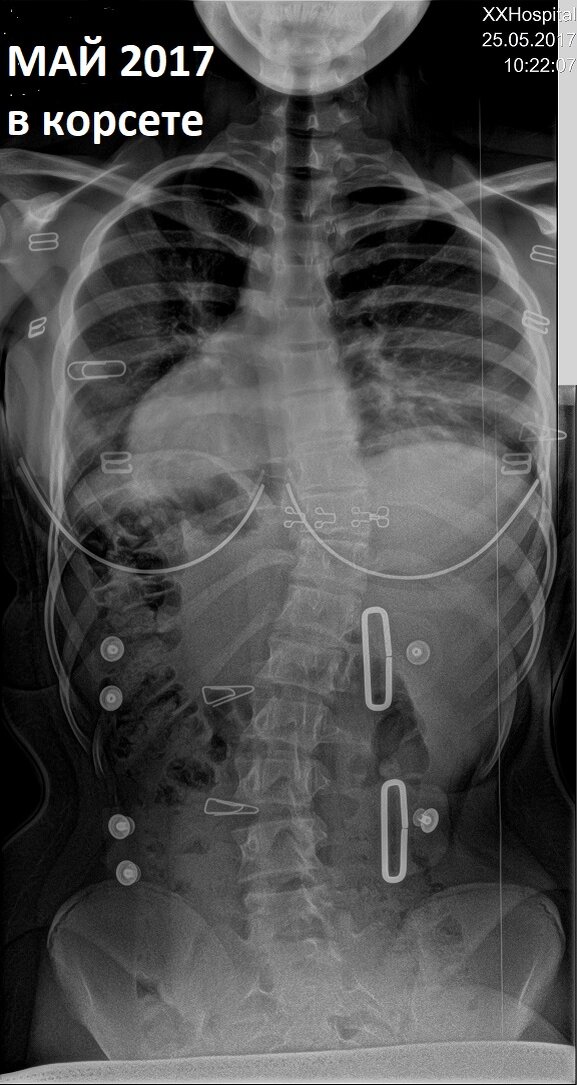

Лечение сколиоза долгое и сложное. Позвоночник не может мгновенно выпрямиться, зато может очень быстро искривиться.

Основная задача корсета - удержать сколиоз, не дать ему развиваться дальше.

Но при правильном ношении корсета в рекомендованном режиме мы наблюдаем изменения в лучшую сторону.

Прошло всего полтора года, а на рентгенах очень хорошо видна положительная динамика.

Девочке 16 лет. Если еще 2 года она будет придерживаться режима, прописанного врачом, у нее есть все шансы войти во взрослую жизнь здоровой и активной.